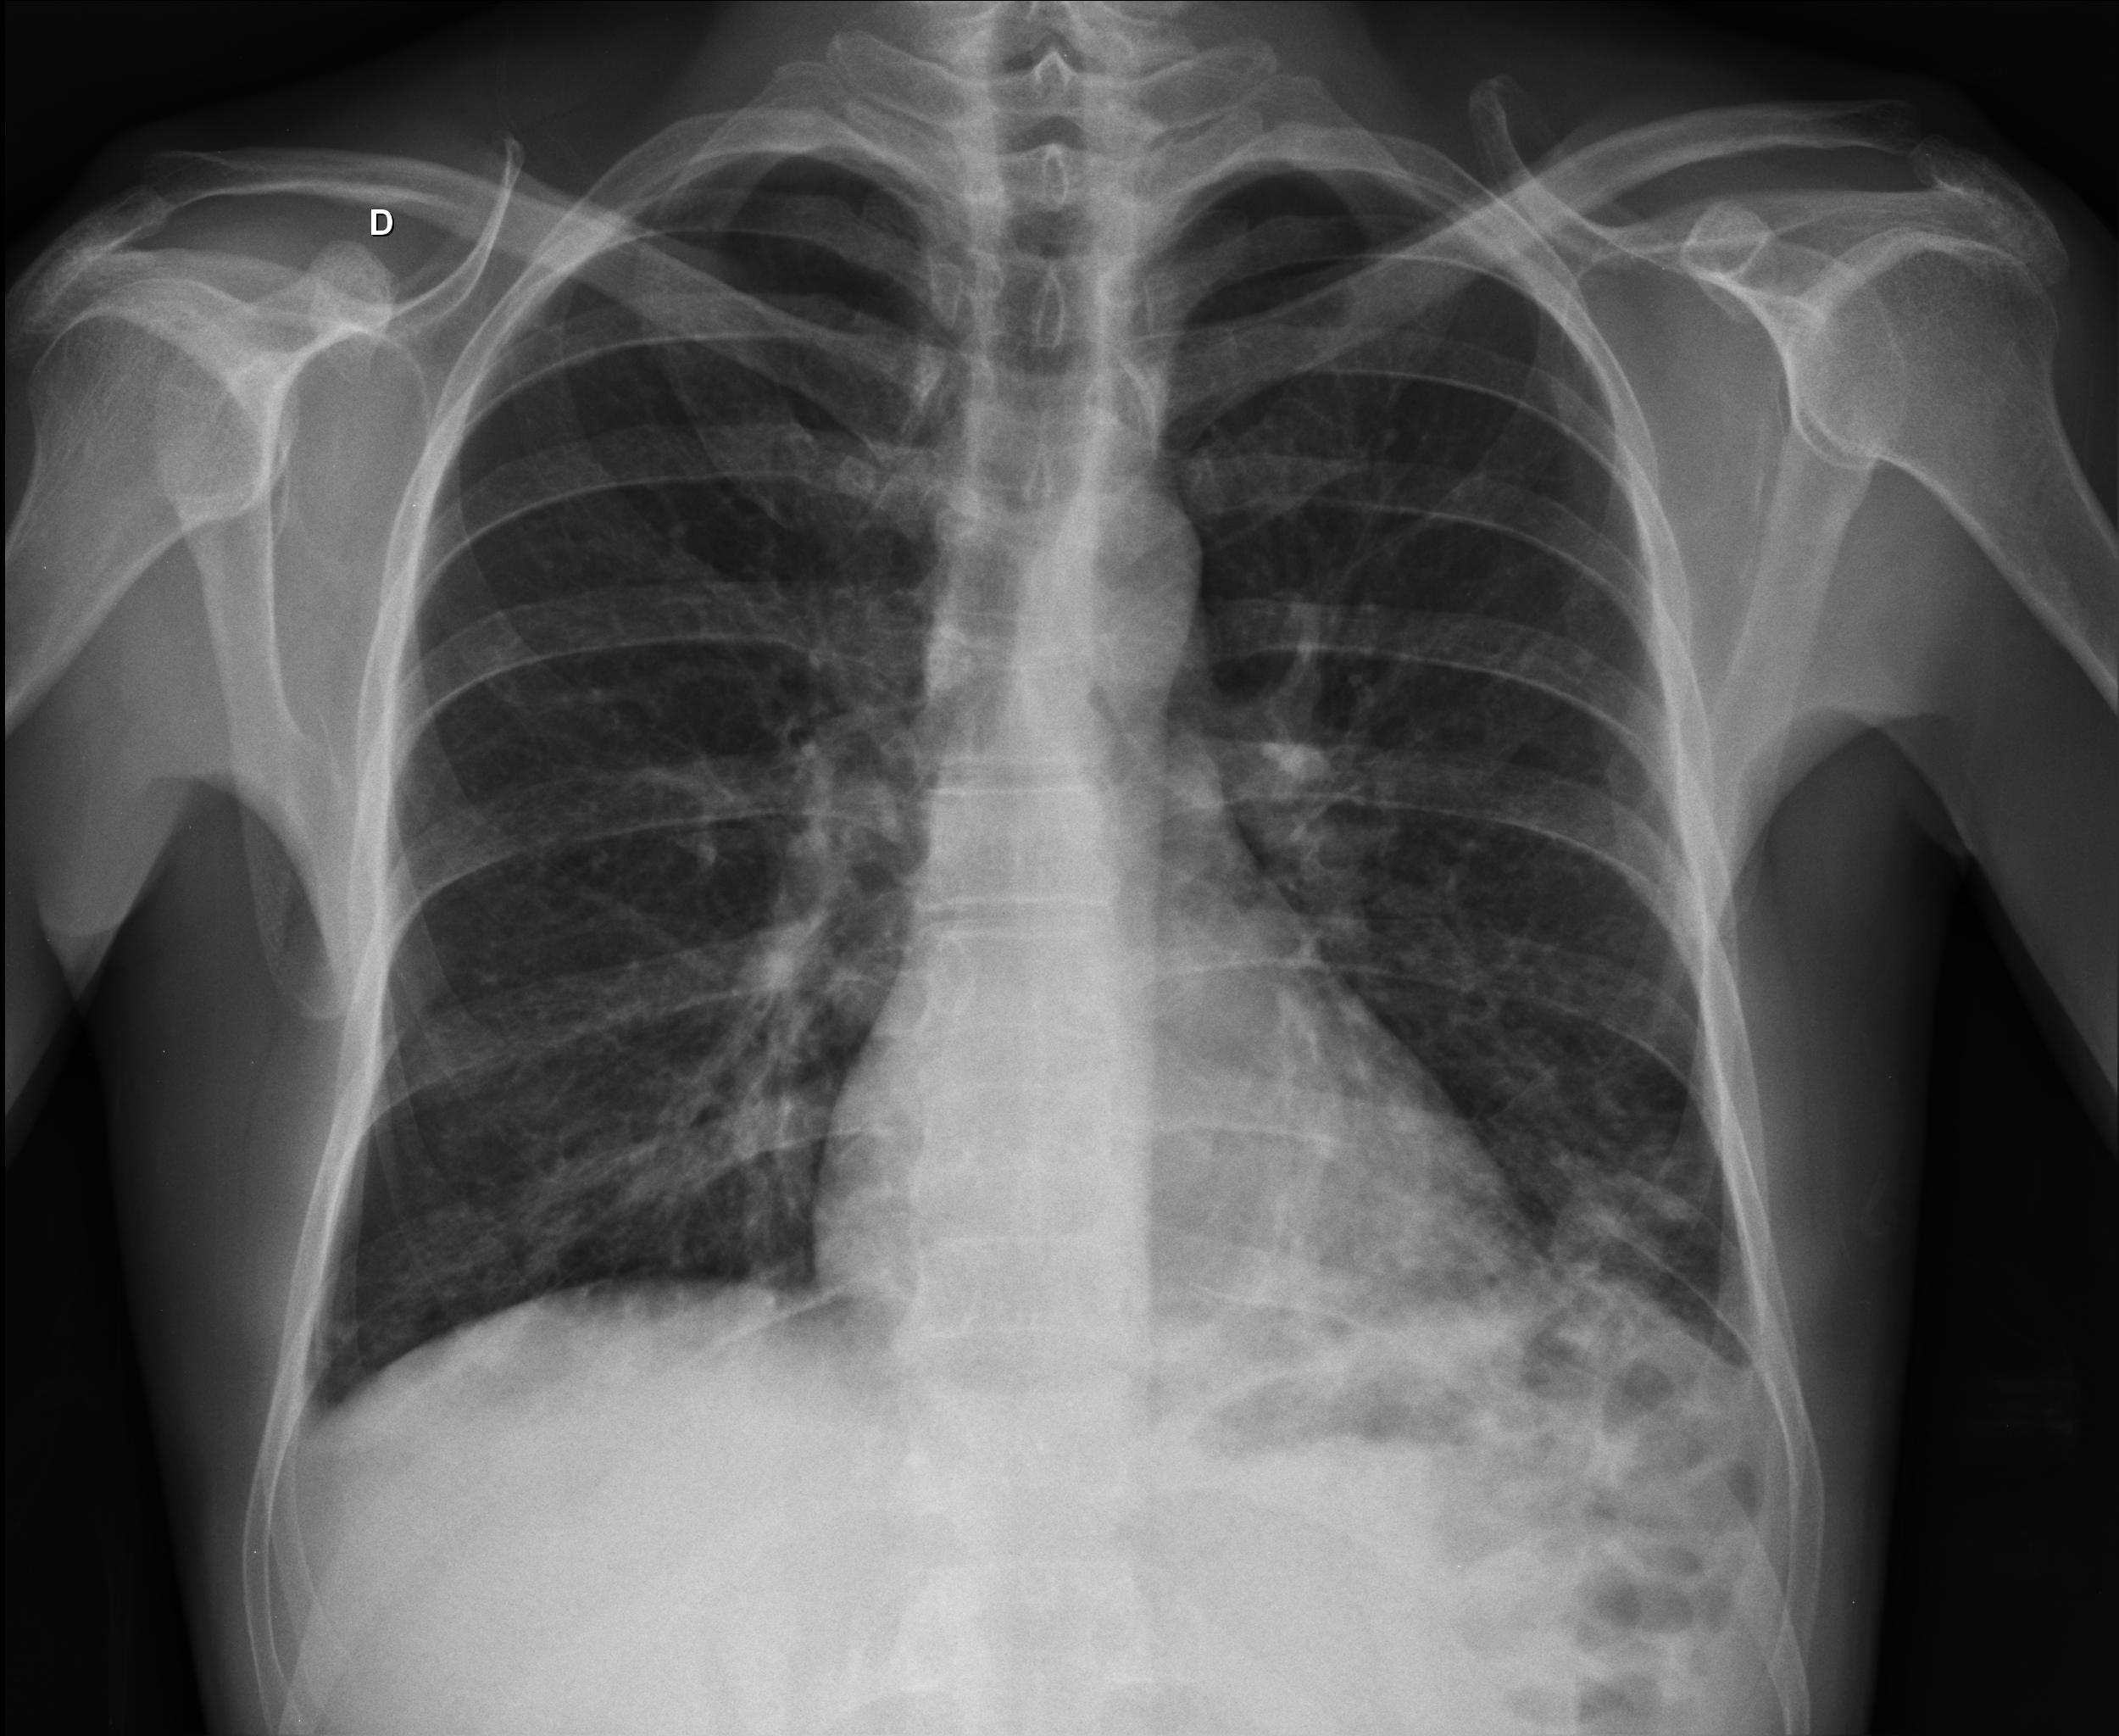

Caso relatado na Reunião de Discussão de Casos Clínicos do Hospital Universitário Prof. Polydoro Ernani de São Thiago, iniciada pelos Profs. Jorge Dias de Matos, Marisa Helena César Coral e Rosemeri Maurici da Silva, em julho de 2017. No dia 14 de junho de 2018, no auditório do HUPEST, realizou-se a apresentação e discussão do caso cujo registro é apresentado a seguir. Trata-se da discussão de onze casos em radiologia torácia, de forma interativa com a plateia, e assim ocorre também neste artigo.